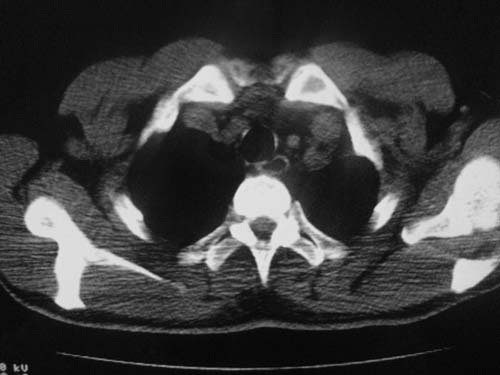

男性39岁,干咳一个月,最近胸憋气短,自己感觉发烧出汗,要求拍ct

图像质量较差请多包含,考虑肺癌,肺结核不除外,大家是否同意这种看法,请各位老师指教

考虑:左肺上叶中央型肺癌并阻塞性肺不张。左肺下叶囊肿或支扩。

左侧肺癌伴阻塞性肺炎,纵隔转移。

1.左侧肺癌伴阻塞性肺炎,纵隔转移。2.左下肺大泡。3.左下肺感染

纵隔淋吧结肿大

心包积液

双侧胸膜增厚

左肺上叶中央型肺癌并阻塞性肺不张,纵隔淋巴结转移。